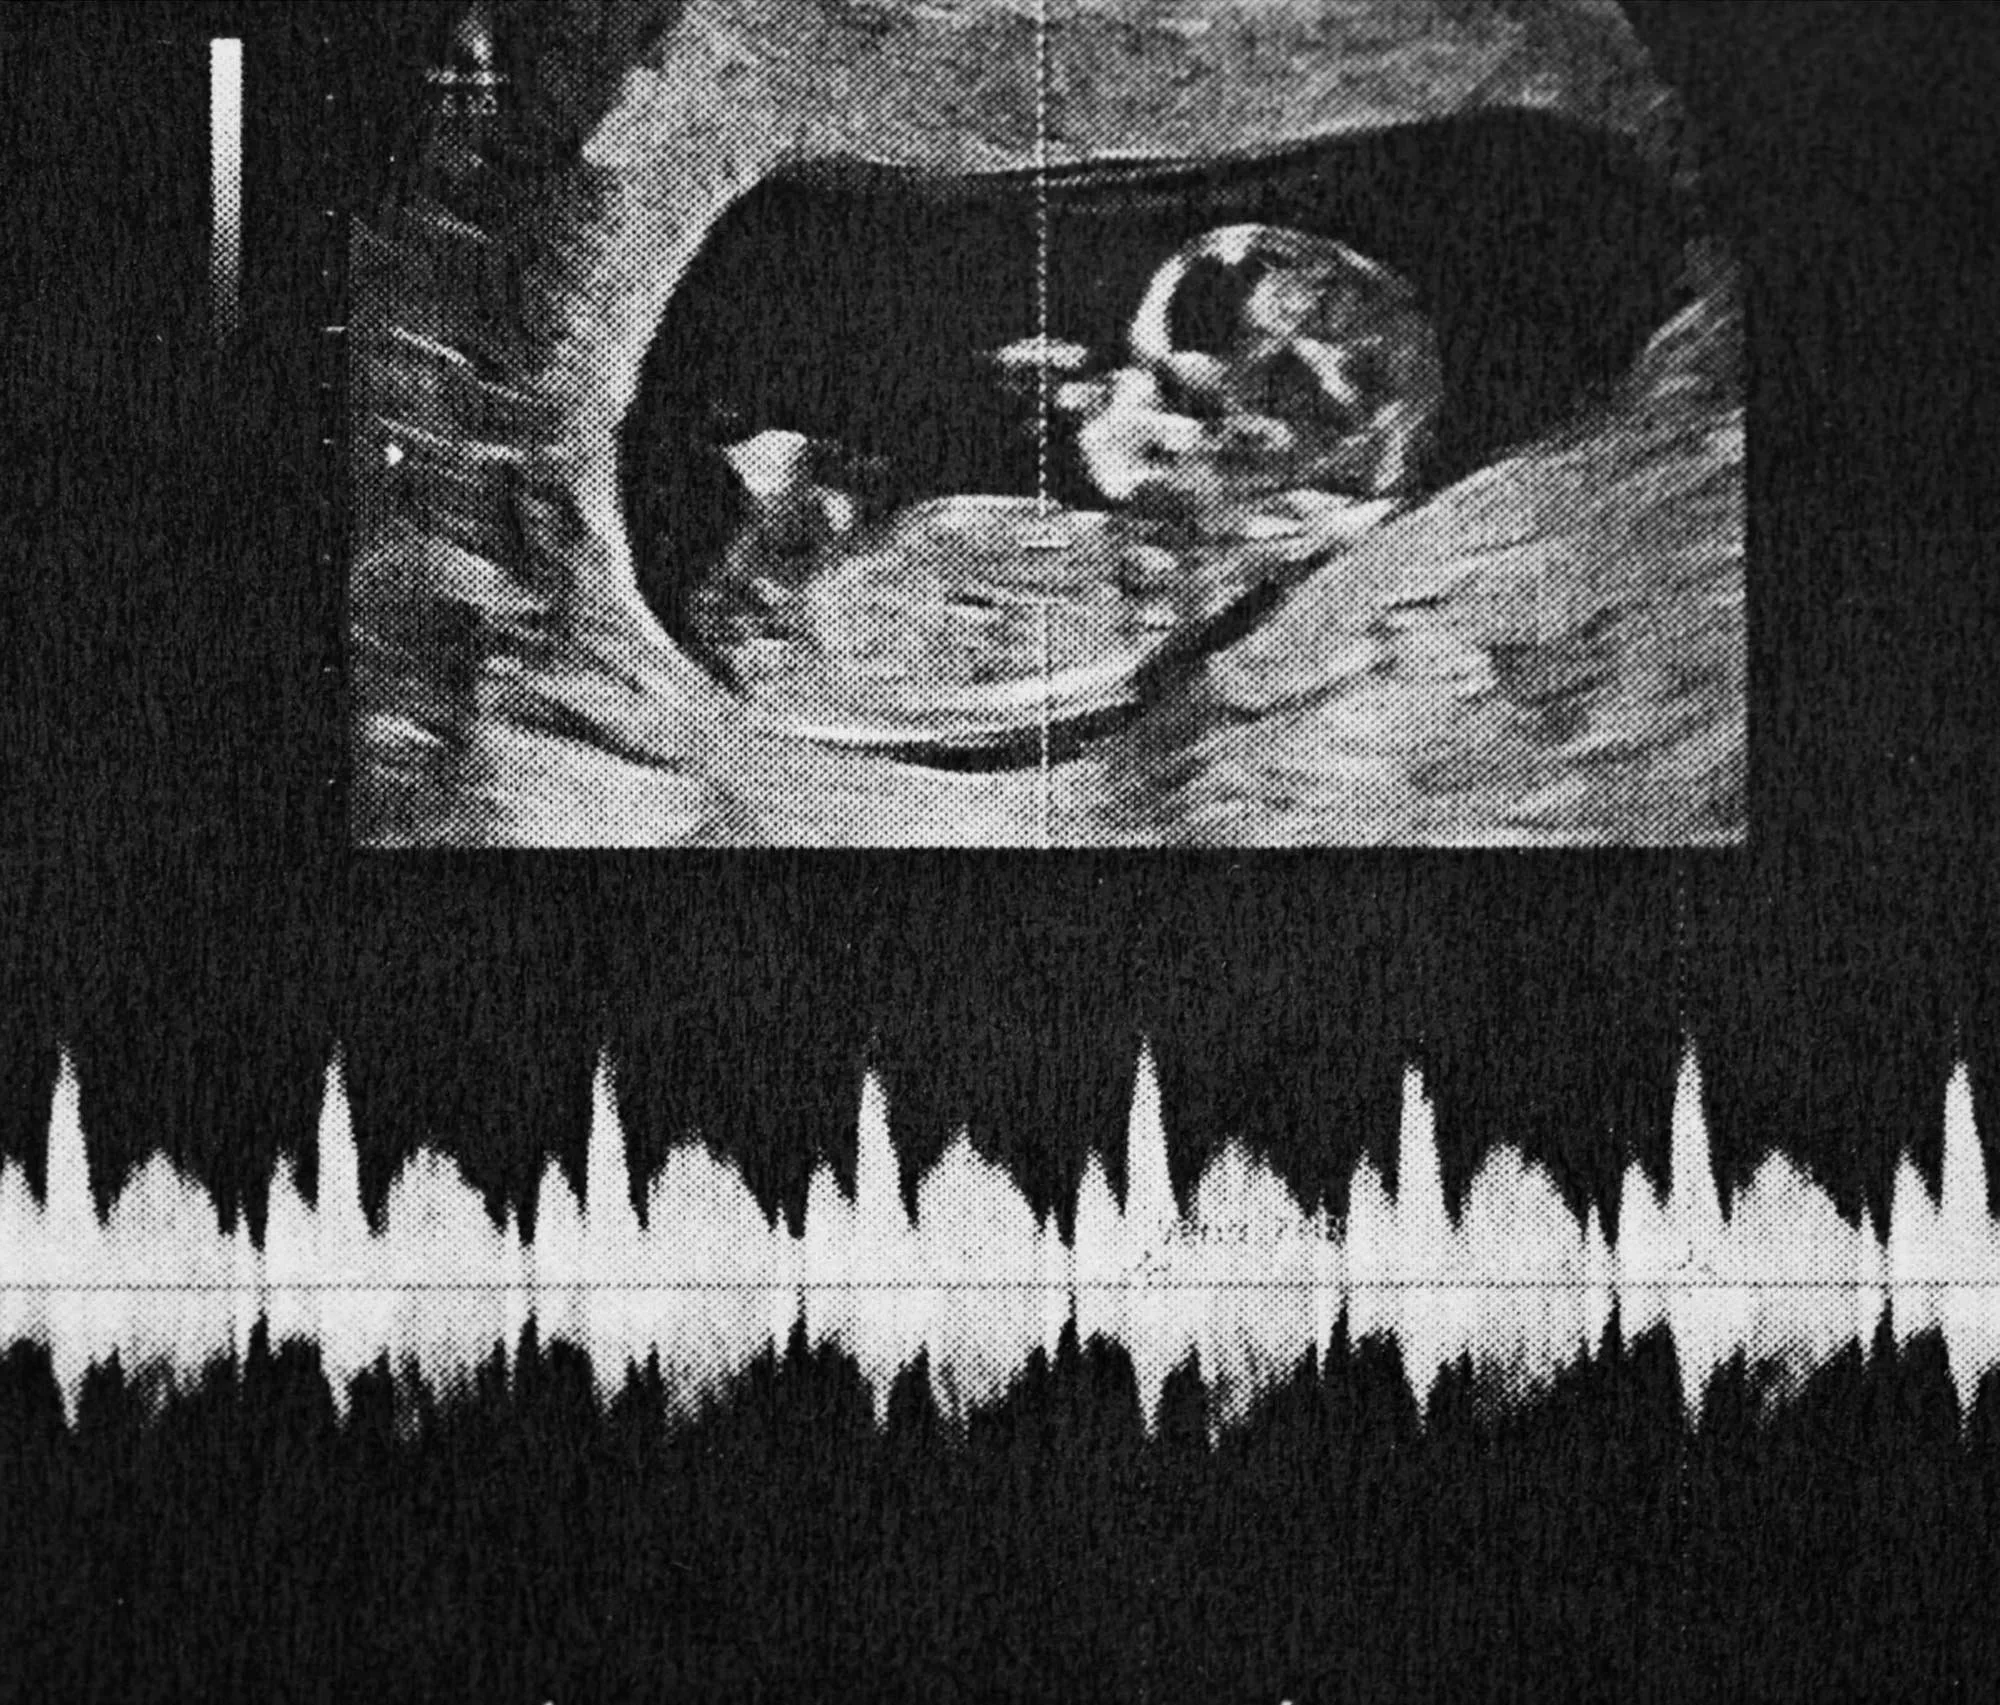

A beginning full of possibility

We understand the weight of this decision, the years that led you here, and the hope you still hold onto. We’ll honor every moment of what comes next.